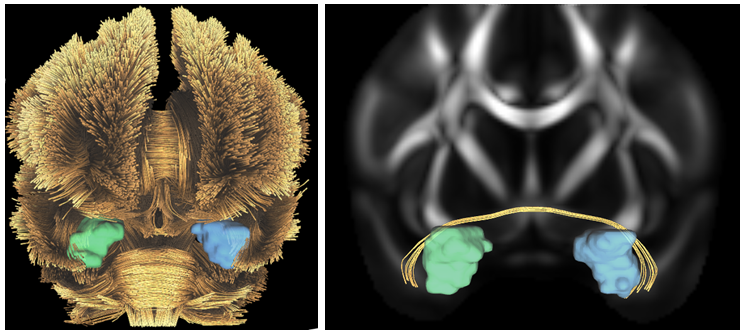

The image processing pipeline of DT-MRI utilizes a T1 weighted MRI image as a registration target for a set of diffusion weighted MRI images obtained by varying the magnetic field direction. The notion behind this novel imaging technique comes from the observation that water molecules will diffuse along the direction of the magnetic field when inside of a fiber traveling in the same direction, producing a high signal. Water molecules will not diffuse outside of a fiber, so a fiber which is perpendicular to the incoming magnetic field will yield a signal of zero. A diffusion tensor is then computed for each voxel that can describe local water diffusion. Sophisticated image pre-processing steps are often required for DT-MRI such as denoising and accounting for other device specific distortions. Each diffusion weighted image is registered to the T1 image, and additional images can be derived from the co-located data such as Fractional Anisotropy (FA), and Directionally Encoded Color (DEC) maps, as shown in Figure 1. The template displayed below was obtained through the Human Connectome Project open dataset and was formed using scans of 842 subjects, 372 of which were male and 470 were female and were between 20-40 years old.5 The FA image shows the major white matter pathways in the brain and can be used along with other derived images such as the DEC map to create other useful data visualizations such as fiber tractography reconstruction. Tractography is an approach to generate 3D models of anatomy out of the major fiber pathways discovered through DT-MRI and can be visualized in a graphics rendering engine. Using a DT-MRI template and derived images from Figure 1, full brain fiber tractography can be generated. Furthermore, fibers emerging from and terminating into specific brain regions, such as the amygdala, can be selected for detailed analysis shown in Figure 2.

Figure 1 Axial representation of the DT MRI processing pipeline. (a) A T1 weighted image is used as a reference image, (b) FA is computed using multiple diffusion weighted images, and (c) a DEC map is created, where colors indicate fiber orientation.

Figure 2 Frontal coronal view of fiber tractography generated using DSI Studio from the Human Connectome project DT MRI data. (a) Full brain fiber tractography with right (green) and left (blue) amygdala shown inside, and (b) Amygdala specific fiber connectivity isolated with FA in the background.